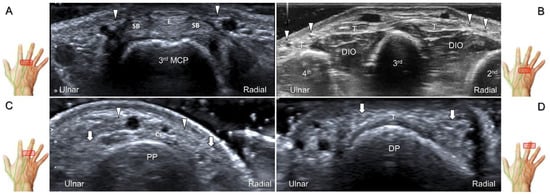

The transducer is positioned on the axial plane of the dorsal metacarpal joint in the target digit. The dorsal proper digital nerves can be found on either side of the sagittal band (Figure 33A). The transducer is moved proximally and the dorsal common digital nerves can be observed superficial to the extensor (usually the extensor digitorum proprius) tendons (Figure 33B). By returning to the level of the sagittal band and moving the transducer distally, the dorsal proper digital nerves can be seen superficial to and alongside the central slip of the finger extensor tendon (Figure 33C). Alternatively, moving the transducer distally toward the proximal phalanx of the first to the radial aspect of the fourth phalanx allows observation of the nerve fascicles of the palmar proper digital nerve originating from the median nerve (Figure 33D).

Figure 33. Sonographic imaging of the dorsal common digital nerve on the metacarpal bone (A), toward the metacarpal head (B). Dorsal proper digital nerves on the proximal phalanx (C), and the terminal nerve originating from the palmar proper digital nerve on the distal phalanx of third finger (D). Arrowheads: dorsal common digital nerve; arrows: palmar proper digital nerve. MCP: metacarpal bone; SB: sagittal band; E: extensor tendon; Cs: central slip; PP: proximal phalanx; T: terminal band; DP: distal phalanx; DIO, dorsal interosseous muscle.